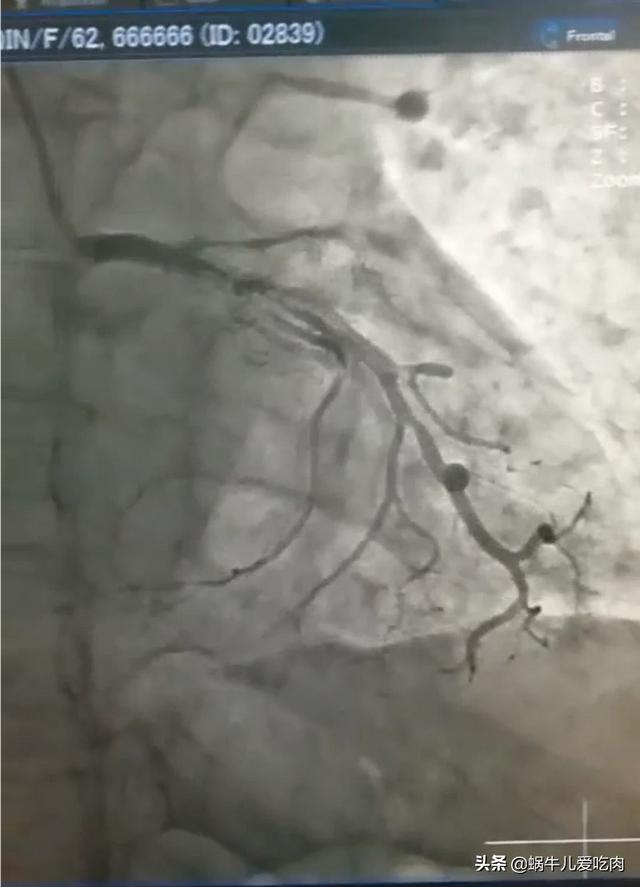

5.冠動脈造影

- 冠動脈造影は検査のために入院が必要で、侵襲的である。

- 冠動脈診断の現在のゴールドスタンダードである、はっきり見えるという利点があり、ある検査で閉塞が非常に深刻であることが判明すれば、再手術の必要なく直接ステントを入れることができる。

でも、その後だ。超音波検査、冠動脈CT、そして特に冠動脈造影検査が行われるようになってから、冠動脈疾患の診断は本当に問題ではなくなりましたこれには、心臓のどの血管がどの程度閉塞しているかを正確に把握することも含まれる。

チューブを心臓に通して選択的に撮影することで、血管を見たいところを見ることができ、血管がどの程度詰まっているかもわかります。

したがって、冠動脈造影は冠動脈疾患の診断のためのゴールドスタンダードであり、冠動脈CTはスクリーニング検査に過ぎないことを忘れてはならない。

6.冠動脈造影冠動脈造影は侵襲的な検査であり、現在でも冠動脈疾患診断の "ゴールドスタンダード "である。.狭窄病変の位置を特定し,その範囲を推定することができる。内腔径が70~75%以上縮小すると血液供給に重大な影響を及ぼすことが一般に認められている。